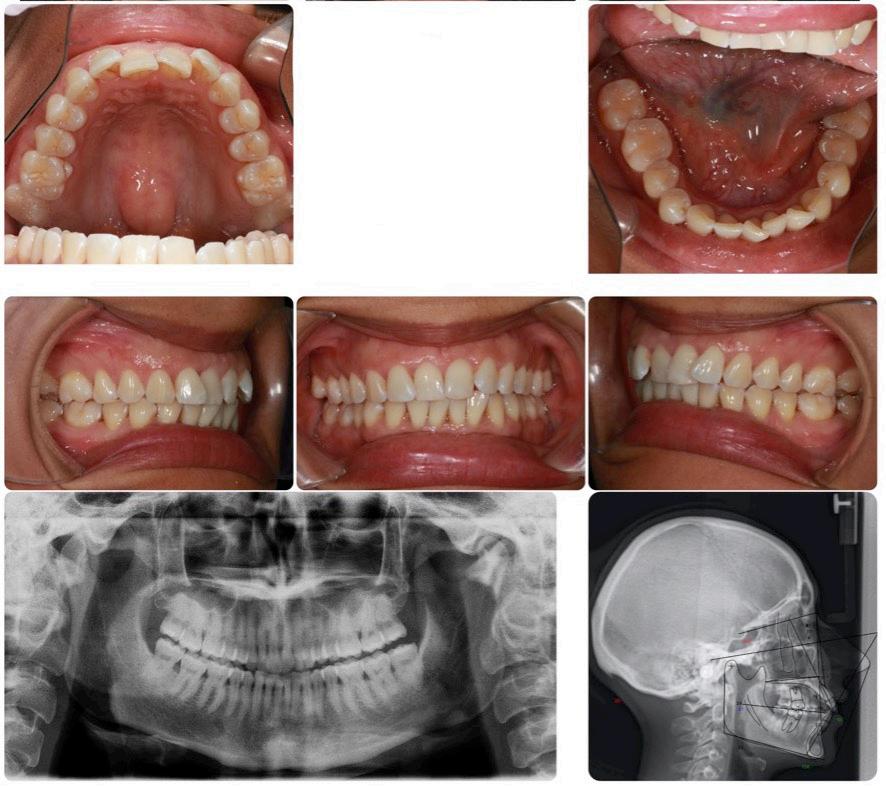

Please view the post-treatment images at the time of insertion of the retainers (Figure 14 - A, B, C. D, E, F, G, H, I, J, K, L, M, N).9

Figure 14H: Post-treatment, mandible, occlusal view

Figure 14I: Post-treatment, posed smile

Figure 14A: Post-treatment, panoramic radiogram

Figure 14B: Post-treatment, cephalometric radiogram

Figure 14C: Post-treatment periapical radiograms

Figure 14D: Post-treatment frontal view

Figure 14E: Post-treatment, right lateral view

Figure 14F: Post-treatment, left lateral view

Figure 14G: Post-treatment, occlusal view

Figure 14J: Post-treatment, posture, frontal view

Figure 14K: Post-treatment, posture, lateral view

Figure 14L: Post-treatment, frontal view

Figure 14M: Post-treatment, lateral view

Figure 14N: Post-treatment, posed smile

Although the treatment was a lengthy one (60 months), our outcome was favourable. The patient was finished with a skeletal class I, an Angle Class I cuspid and a Class II molar relationship with minimal overjet and overbite. ANB stayed the same however, Wits improved from -5.0 mm to 2.0 mm. ALFH increased by 7.0 mm due to the composite build-ups on the mandibular first molars and elevation of the rest of the mandibular dentition to this height. Also, the growth from CVMS 2 - 3 to CVMS 5 influenced the height of the mandibular alveolar process. The patient’s posture did not change significantly as the frontal view still revealed a slight left head tilt, and the lateral view revealed the head forward position seen previously. We postulate that the lack of greater improvement in posture relates to untreated nasal airway impingement. Olmos writes that nasal airway compromise is thought to exacerbate forward head posture, worsen unfavourable growth patterns (hyperdivergence) and contribute to mouth breathing as the patient is attempting to maintain a better airway.10 It is possible that advancement of the maxilla may have

The position of the anterior teeth was more favourable, U1/SN 93° to 109°, L1/GoM 83° to 91°. The Naso-labial angle became more obtuse from 110° to 118°. The Facial axis (Growth axis –Ricketts) changed to a more ideal value, from 83° to 92°, due to the odontectomy of two maxillary first bicuspids.

The final panoramic radiogram reveals impacted wisdom teeth and distally tipped mandibular second molars that partially erupted. The final periapical radiograms of the maxillary anterior teeth reveal minimal root resorption and acceptable angulation except for #12(7), where the root remained distally oriented.